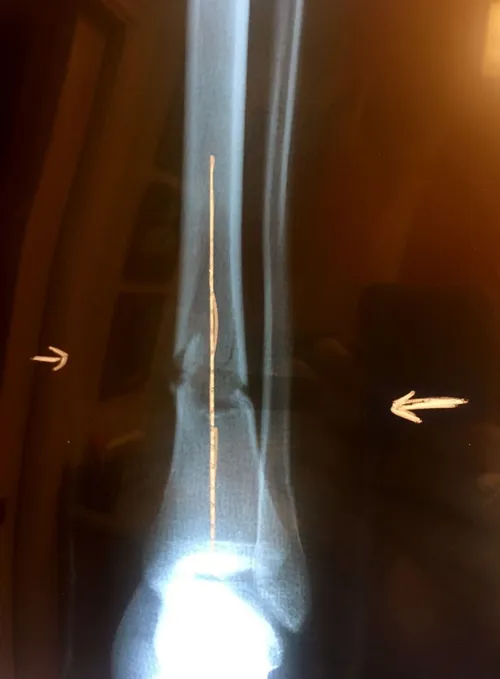

Below, Tibia and Fibula Fracture in a 16-year-old injured skiing. The patient presented to the office 8 days after injury with a displaced fracture. The first 2 films show the displacement in the fracture of the tibia. After an above knee cast is applied, the cast is wedged under fluoroscopy and new xrays show the near perfect reduction of the fracture. The white arrows show the area where the cast is wedged

Wedging of cast to keep a tibia fracture well aligned. We wedge the cast on a side if there is malalignment early on in the fracture healing to realign the fracture